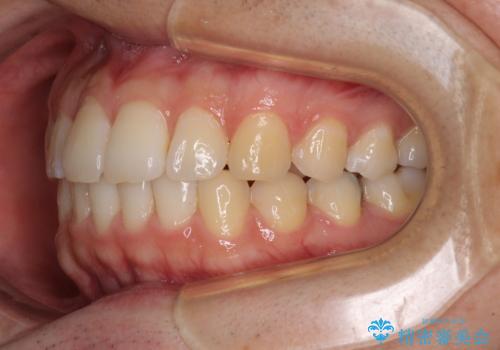

インビザライン・ライトによる矯正治療の後戻り改善

- 矯正治療の後戻りを気にして来院された患者様です。

後戻りは軽微でしたので、インビザライン・ライトにより矯正治療を行うこととしました。

再矯正後の後戻りを防ぐため、歯列排列後に、下顎前歯はワイヤーによる固定を行いました。

下顎前歯の歯列を動かないようにしておくことで、上顎前歯の後戻り防止にも効果を発揮します。